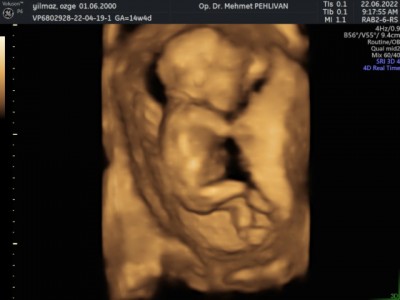

pipi veya testis görmedi yapısını erkeğe benzetti sizce değişme olur mu bu haftalarda böyle tahminde bulunup değişen oldu mu

Gebelik haftası 14+4

Bende 14+4 tteyim günü gününe bi anne bulur muyum diye düşünüyordum , bize 13+2 de erkek demişti ama %100 demedi , bazen göbek kordonu ile pipiyi karıştırabilirler